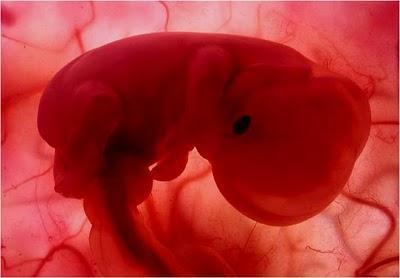

UN EMBRIÓN DE POCAS SEMANAS QUE SE ENCUENTRA EN EL INTERIOR DEL ÚTERO DE SU MADRE.

ESTÁ EN EL INICIO DE SU DESARROLLO.

ES APENAS EL PRINCIPIO DE UN SER HUMANO Y EN ESTE ESTADO PODRÍA SER CONFUNDIDO CON EL EMBRIÓN DE UN MACACO.

JUNTO A ÉL SE ENCUENTRA EL SACO VITELINO,PROPORCIONÁNDOLE LOS NUTRIENTES QUE NECESITAEN LAS PRIMERAS SEMANAS DE VIDA.

ALREDEDOR DE LA 8ª SEMANA DE GESTACIÓN EL SACO VITELINO PIERDE SUS FUNCIONES. EL CORDÓN UMBILICAL EMPEZARÁ AALIMENTARLO CON NUTRIENTES TOMADOS DELCUERPO MATERNO A TRAVÉS DE LA PLACENTA.

MIENTRAS TODO ESTO SUCEDE, ÉL FLOTA TRANQUILAMENTE,EN EL ÚTERO DE SU MADRE.